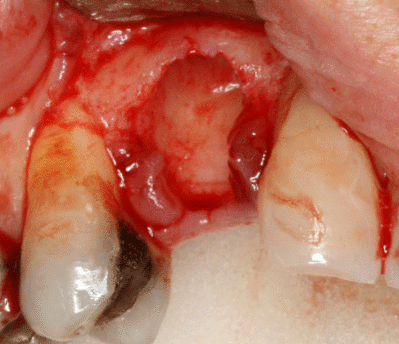

Разборный имплантат состоит из непосредственно имплантата и надстройки (супраструктуры), именуемой абатментом. Такой имплантат может быть установлен по одно- и двухэтапному протоколу. Двухэтапный протокол подразумевает полное погружение имплантата и накрывание его слизистой оболочкой, в результате чего исключается любой контакт имплантата с полостью рта — эта процедура называется первым этапом дентальной имплантации. Второй этап заключается в установке какой-либо надстройки (супраструктуры) — это может быть как формирователь десны, так и абатмент с временной коронкой или другим видом протезной конструкции. После какого промежутка времени будет выполнен второй этап обычно решает имплантолог, опираясь на данные о качестве костной ткани, возраст и общее состояние пациента, а также свой клинический опыт. Классические сроки составляют 4—6 месяцев, однако последнее время существует тенденция к сокращению сроков ожидания до 2,5—3 месяцев. Это связано с лучшим пониманием процесса остеоинтеграции, а также оптимизацией макродизайна и микрохарактеристик поверхности имплантатов.

Техника

При планировании зубных имплантатов основное внимание уделяется общему состоянию здоровья пациента, местному состоянию здоровья слизистых оболочек и челюстей, а также форме, размеру и положению костей челюстей, соседних и противолежащих зубов.